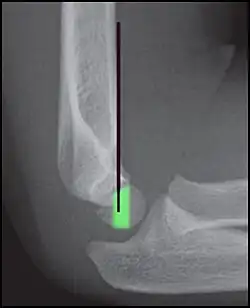

Anterior humeral line - It is a line drawn down along the front of the humerus on the lateral view and it should pass through the middle third of the capitulum of the humerus.[9] If it passes through the anterior third of the capitulum, it indicates the posterior displacement of distal fragment.[8]

Anterior humeral line (black line), with normal area passed on the capitulum of the humerus colored in green in a 4-year-old child.[9] -